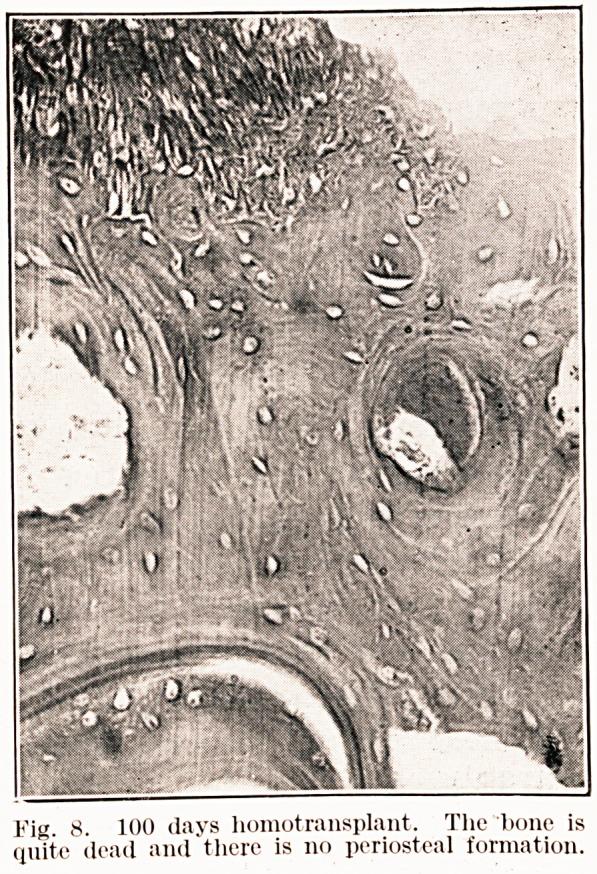

Observations on bone transplants in the anterior chamber of the eye.